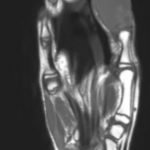

Magnetic resonance imaging (MRI) showed an “expansile, destructive solid and cystic mass with aggressive…characteristics…” (see images). Tissue biopsy confirmed a giant cell tumor arising from the bone. The patient underwent a debulking procedure, and later a distal amputation. Follow-up on pathology showed negative margins.

The best imaging study is MRI, to assess for bony and tissue involvement and surgical approach. Computed tomography may be used; however, it doesn’t delineate the soft tissue and bony connections as well. Standard oncology labs should be drawn as well, including: CBC with differential, LDH, uric acid, CMP, ESR. The growth of the tumor is insidious and therefore imaging should be done based on clinical concern. In the ED setting, if close follow up can be ensured, imaging can be done as an out-patient. Annual surveillance is recommended for at least five years in most patients, even after total resection, according to some studies.3